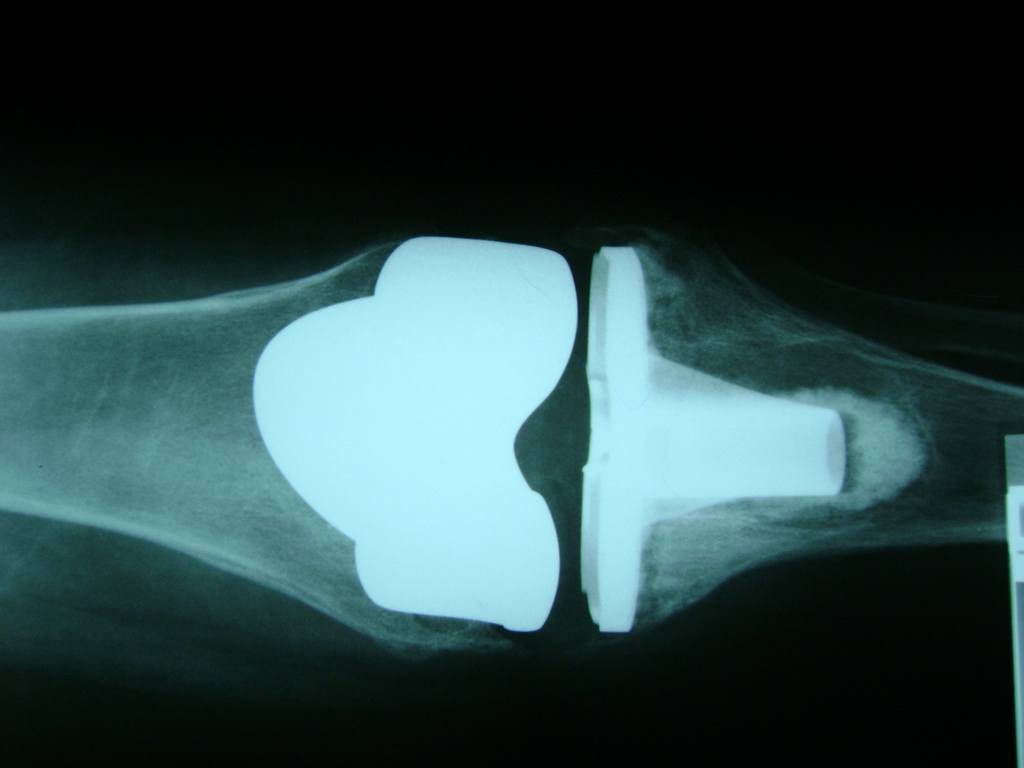

Fémur - Rodilla